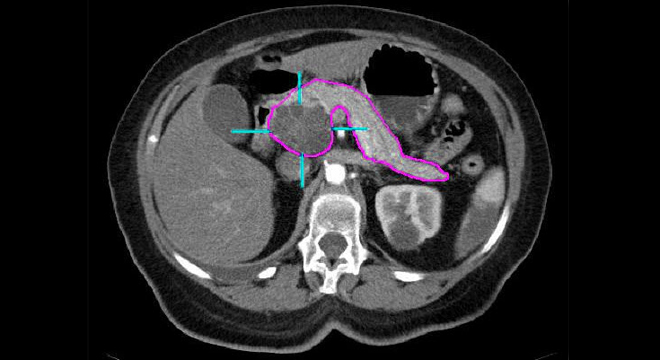

Bauchspeicheldrüsenkrebs: Computertomographie

• Computertomographie (CT)